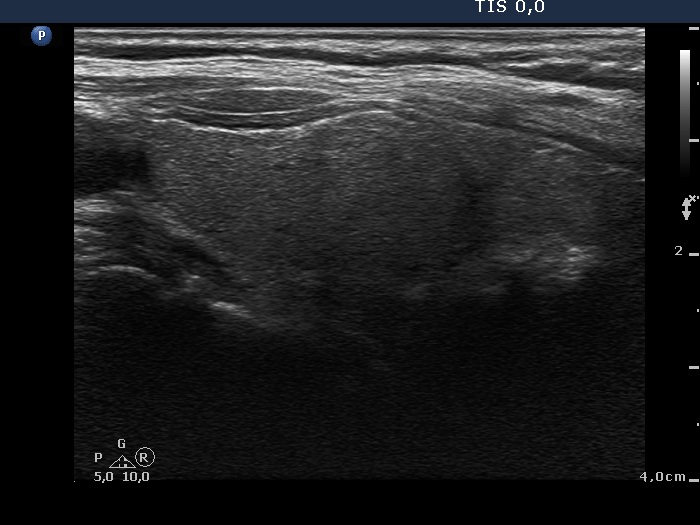

Ultrasonography: the right thyroid was echonormal while the left lobe contained moderately hypoechogenic areas with a 50% echogenicity index. There was a hypoechogenic mass lower and lateral to the right thyroid. The lesion did not present a regular hilum.